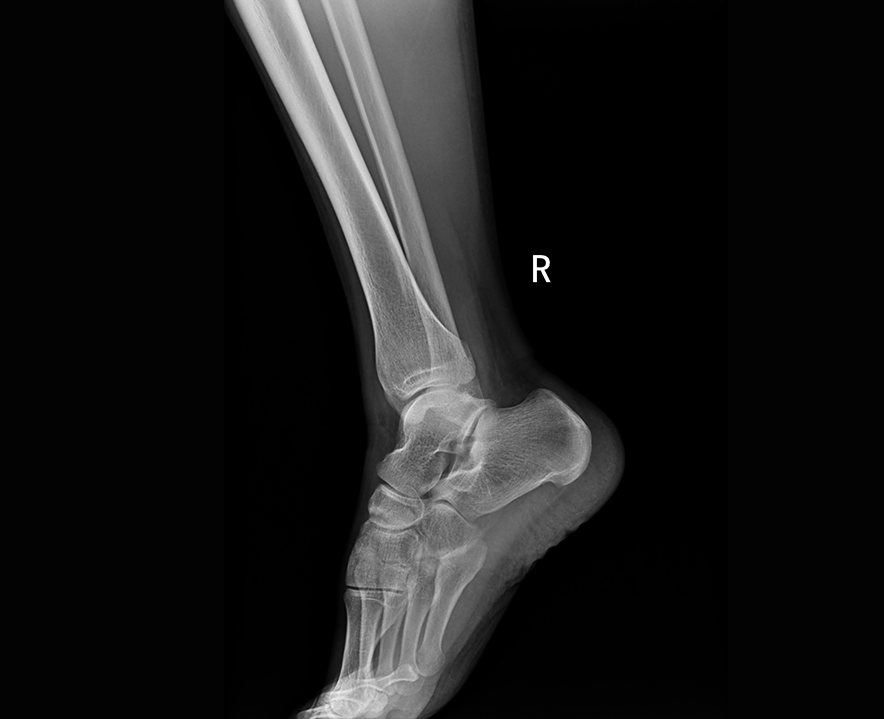

自主研發高頻逆變高壓發生器,配合高效自主增強圖像處理技術,呈現清晰細膩的圖像效果。